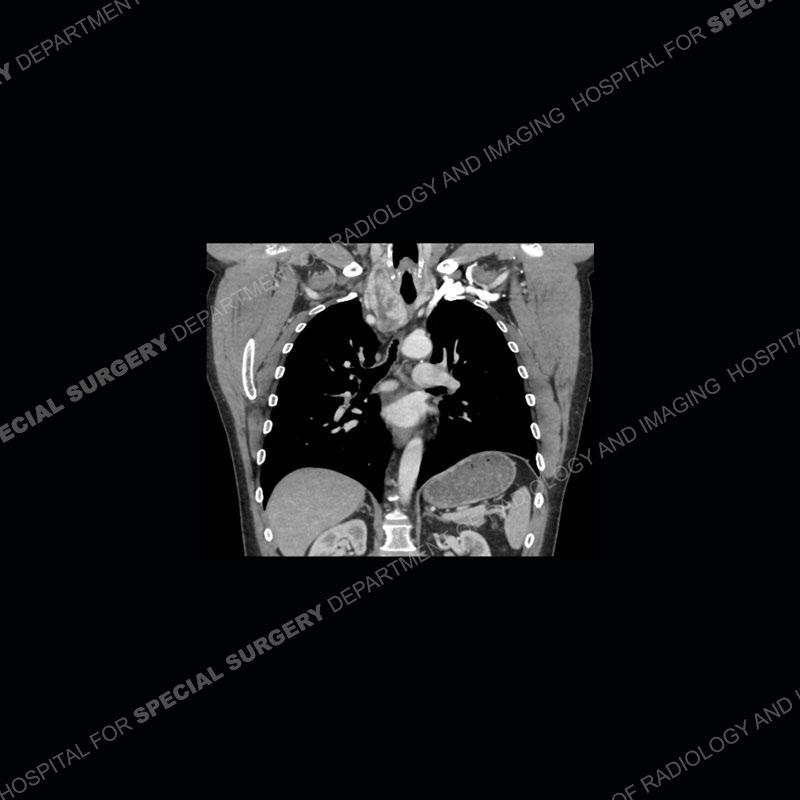

Findings

The chest radiographs demonstrate a leftward deviation of the trachea. CT images demonstrate a large, somewhat heterogeneous mass of the thyroid that extends outside the confines of the thyroid tissue. There is a subtle, enhancing soft tissue mass of the proximal right humerus. Slightly prominent mediastinal lymph nodes are present with additionally, multiple supraclavicular lymph nodes.

Over the years we have shown a couple of these cases which may be considered more so an “eye test” then anything else. In clinical practice, these are often very difficult cases as the initial finding of the tracheal deviation may be easily overlooked. Screening radiographs are clearly most often used to assess cardiopulmonary function before induction of anesthesia but at times other findings of great and unfortunately grave consequence can be found. The evaluation of the incidental thyroid mass on CT and MRI is an ever changing situation. Parameters such as age of patient, extension outside of the thyroid, enhancing nodules, and local invasion of lymph nodes are evaluated to see if a lesion needs to be further evaluated.

Although not strictly a part of the evaluation of an “incidental” thyroid lesion, evaluation of the adjacent lymph nodes and bony structures can also be quite important. In this case, there is an enhancing mass of the right humerus. This is very subtle and can only really be recognized by evaluating the density of the bone. Typicaly marrow will have a fatty density or nearly fluid density. As the density, as in this case, approaches soft tissue an infiltrative process must be entertained. Thyroid mets are markedly vascular accounting for the areas of enhancement of the humeral mass. The mediastinal and supraclavicular lymph nodes although not individually enlarged, should raise suspicion of an underlying inflammatory/neoplastic process.